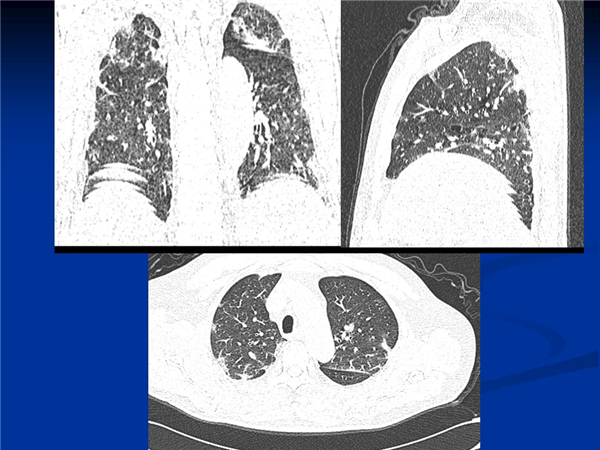

【病例分享】新型冠狀病毒感染肺部CT影像4例(常德市第一人民醫(yī)院)

幻燈片5.jpg

幻燈片7.jpg